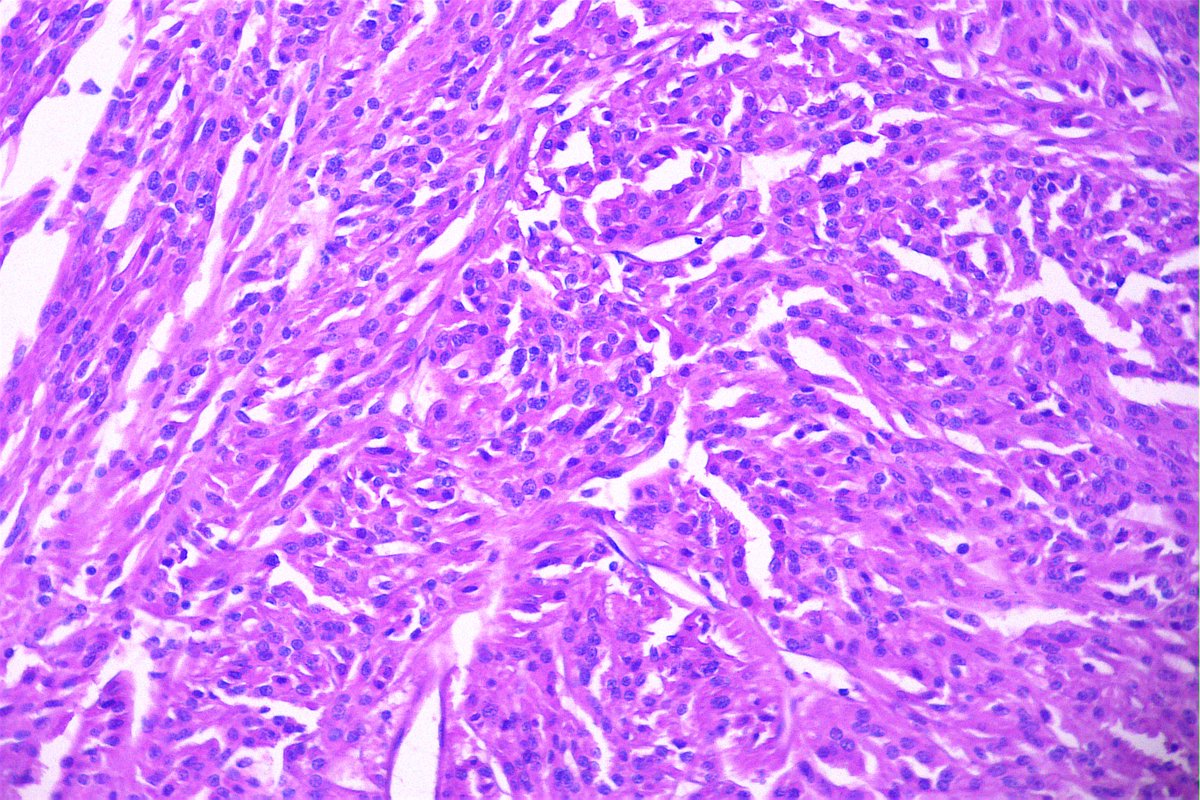

@GeronimoJrLapac

Ger么nimo Jr.

2 months

Breast. Carcinoma or inflammatory? #breastpath